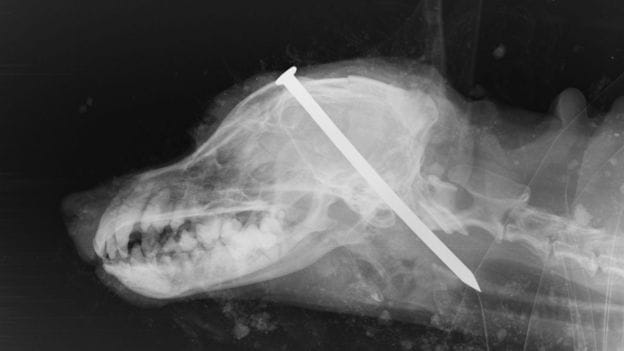

D'autres cas de cruauté animal ont provoqué des débats autour de la sévérité des peines rendues. Les deux hommes qui ont tenté de tuer un chien en lui enfonçant un clou dans le crâne ne feront, par exemple, que deux mois de prison.En Angleterre, la peine maximum pour les tortionnaires d'animaux est de six mois, la sentence la plus faible de toute l'Europe. D'après la BBC, 3000 personnes ont été reconnues coupables de cruauté envers un animal entre 2013 et 2015, mais seuls 7 % des accusés ont écopé d'une peine de prison.